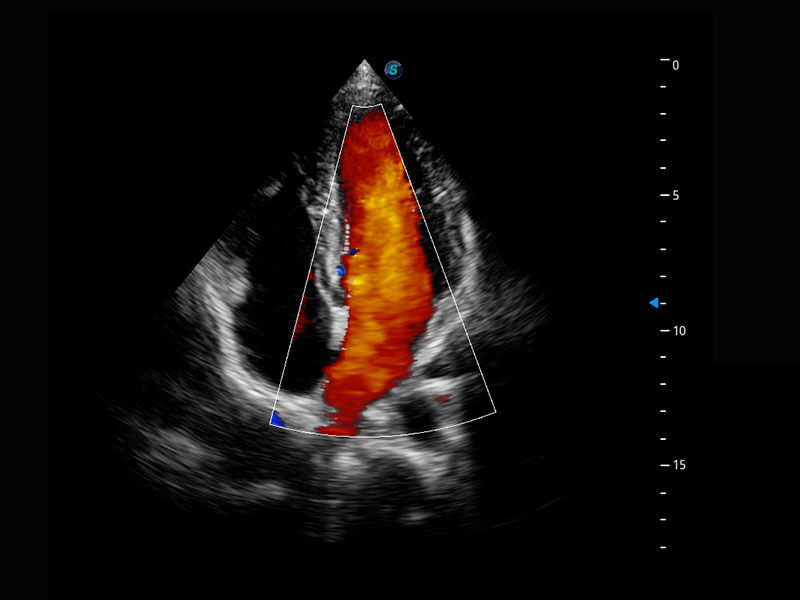

四腔心血流

P60搭载一系列胎儿心脏成像技术,实现精细的胎儿心脏评估。